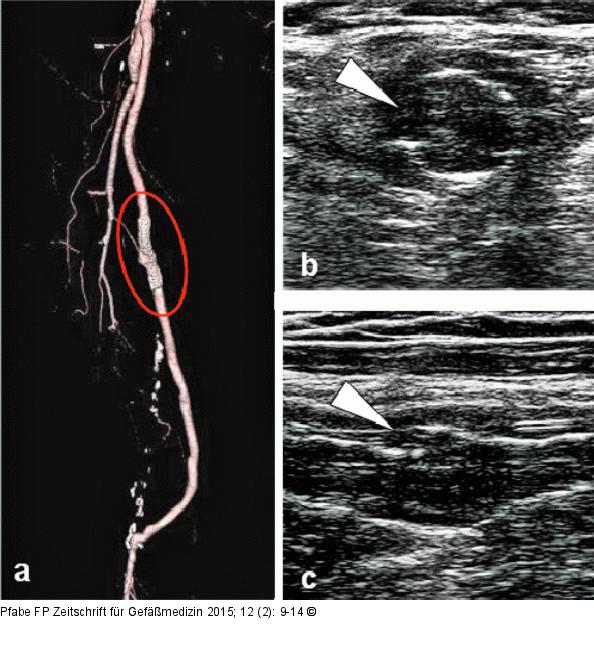

Abbildung 6a-c: Stentfraktur Typ III Pseudoaneurysma bei Stentfraktur Typ III in der bildgebenden Diagnostik. (a): Kontrastmittelverstärkte CT-Angiographie (VRT); (b): sonographische Darstellung der Stentfraktur Typ III im B-Mode (Querschnitt) mit Visualisierung der Kontinuitätsunterbrechung des Stents (weißer Pfeil), links lateral thrombosiertes Pseudoaneurysma; (c): sonographische Darstellung (Längsschnitt) der Stentfraktur Typ III (weißer Pfeil). |

Pseudoaneurysma bei Stentfraktur Typ III in der bildgebenden Diagnostik. (a): Kontrastmittelverstärkte CT-Angiographie (VRT); (b): sonographische Darstellung der Stentfraktur Typ III im B-Mode (Querschnitt) mit Visualisierung der Kontinuitätsunterbrechung des Stents (weißer Pfeil), links lateral thrombosiertes Pseudoaneurysma; (c): sonographische Darstellung (Längsschnitt) der Stentfraktur Typ III (weißer Pfeil). |